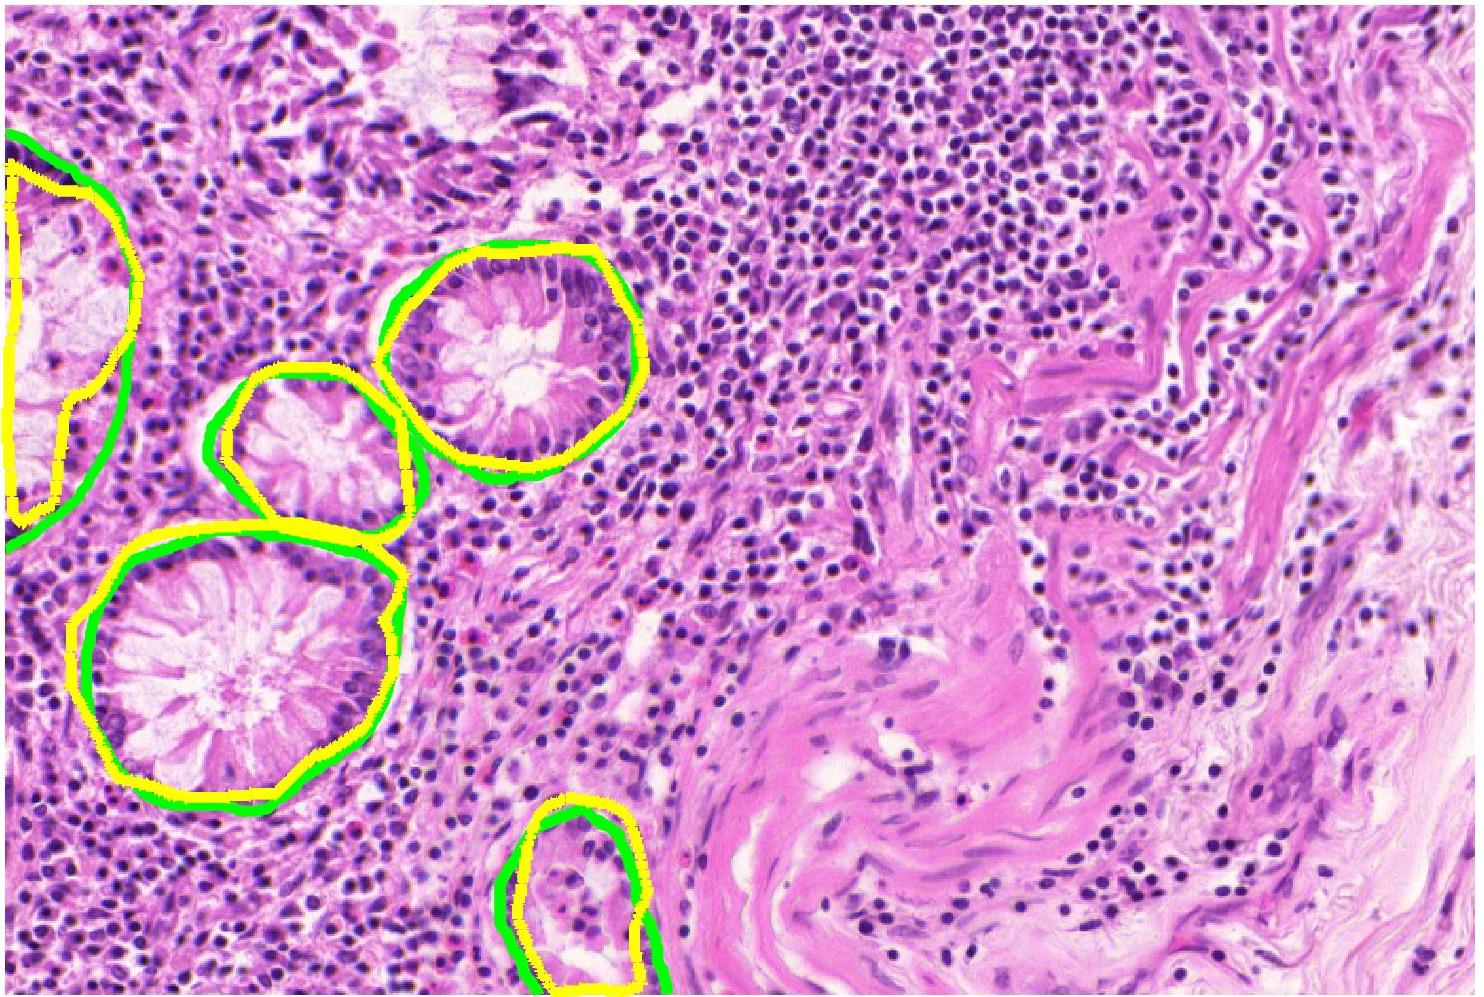

Ground truth maps obtained from the semi-supervised learning step has labels for each block. Consequently, there will be cases where a pixel outside the actual structure of interest shares its label since it is part of the block. This erroneous labeling is referred as label noise. Our experimental results show that the UNet++ network is more robust to such label noise than the conventional UNet. Figure 4 shows comparative results of using UNet and UNet++ in obtaining the weak segmentation map. UNet++ proves to be more robust to initial label noise. Figure 5 shows example images, their corresponding expert annotated manual segmentation maps, and the maps obtained using our method. A very high degree of agreement exists between weak supervision generated maps and the ground truth, with a Dice Metric of validating this observation. Without the label refinement step we obtain a Dice Metric of , highlighting its contribution in improving segmentation performance. Using UNet we obtain a Dice metric of and (without label refinement), which indicates superior capacity of UNet++ to overcome label noise. Thus we repose high confidence in the weakly supervised generated label maps as representing the correct labels and are reliable enough to model inter-label geometric relationship (as described in the next step).

We apply our method on the public GLAS segmentation challenge [189], which has manual segmentation maps of glands in stained images derived from histological sections from different patients with stage or colorectal adenocarcinoma. The slides were digitized with a Zeiss MIRAX MIDI Slide Scanner having pixel resolution of m. The WSIs were rescaled to a pixel resolution of m (equivalent to magnification). visual fields from malignant and benign areas from the WSIs were selected to cover a wide variety of tissues. An expert pathologist graded each visual field as either ‘benign’ or ‘malignant’. Further details of the dataset can be found at [189].

We generate augmented images using GeoGANWSS and train a UNet++ segmentation network to obtain the final output. The performance metrics - Dice Metric (DM), Hausdorff distance (HD), F1 score (F1)- for our results (including ablation studies) and top-ranked methods [190, 189] are summarized in Table V. The numbers are taken from the challenge paper in [189] (Table 2). Except for GeoGANManual (equivalent to fully supervised training), our method, GeoGANWSS, outperforms all other methods using a standard segmentation architecture. The ablation study experiments’ performance also demonstrates the benefits of including all components of our proposed method. Competing methods in the challenge have used conventional augmentation, whereas our image synthesis approach generates more informative images.

Figure 8 shows example segmentation outputs of GeoGANWSS and other variants of our method used for ablation studies. The results clearly show that with the exclusion of our proposed method’s different components, the segmentation performance degrades.